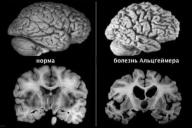

болезнь Альцгеймера